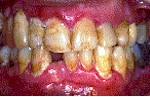

Periodontitis Leve.- Sangrado más pronunciado e hinchazón en las encías, las encías comienzan a despegarse de los dientes, mal aliento y gusto, bolsas de 3-4 mm de profundidad.

Periodontitis Moderada.- Los dientes se ven más largos debido a la retracción, pueden desarrollarse abscesos, mal aliento y mal gusto, los dientes pueden comenzar a moverse y a mostrar espacios, bolsas de 4-6 mm de profundidad.

Periodontitis Avanzada.- La movilidad dentaria puede incrementarse, Mal aliento y mal gusto constantes,  Sensibilidad dentaria debido a la exposición de las raíces, Bolsas mayores a 6 mm, Pueden perderse algunos dientes.